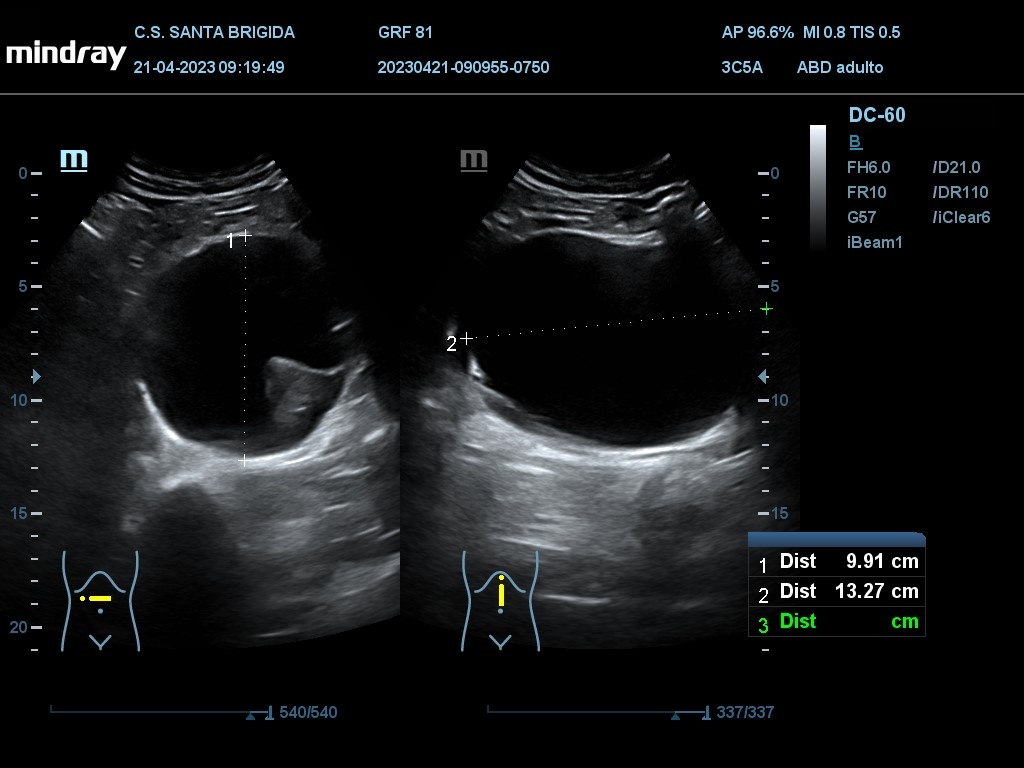

En ecografía clínica se aprecia dilatación de aorta abdominal de extensión máxima de 13,27 cm con origen proximal a la bifuración de las arterias renales y con un diámetro máximo de 9,91 cm. Además asocia imagen hiperecogénica respecto a la luz del vaso en la práctica totalidad de su recorrido en probable relación con trombo intramural semilunar de 3,7 cm.